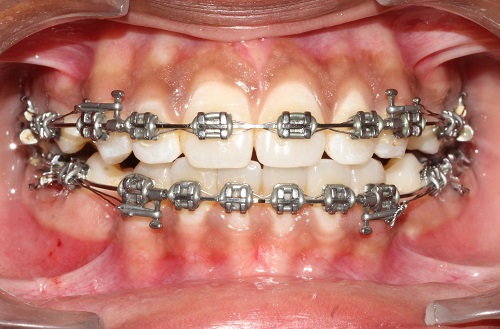

The various treatment offered in the department includes fixed orthodontic treatment with metal, ceramic,self-ligating brackets, treatment with mini-implants, Rapid Maxillary Expansion appliances, orthognathic surgeries to correct facial deformities, distraction osteogenesis procedures with Internal and External distractors, treatment of cleft lip and palate, Pre-surgical Naso Alveolar Moulding on cleft cases, Fixed functional treatment with Forsus, Powerscope, Herbst etc, Lingual Orthodontic treatment, Myofunctional Appliance Therapy, Aligner Orthodontic Treatment ,Myofunctional trainers, Splints- For Temporomandibular joint disorders as well as Class III correctors in growing individuals with appliances such as Tandem Traction Bow Appliance.